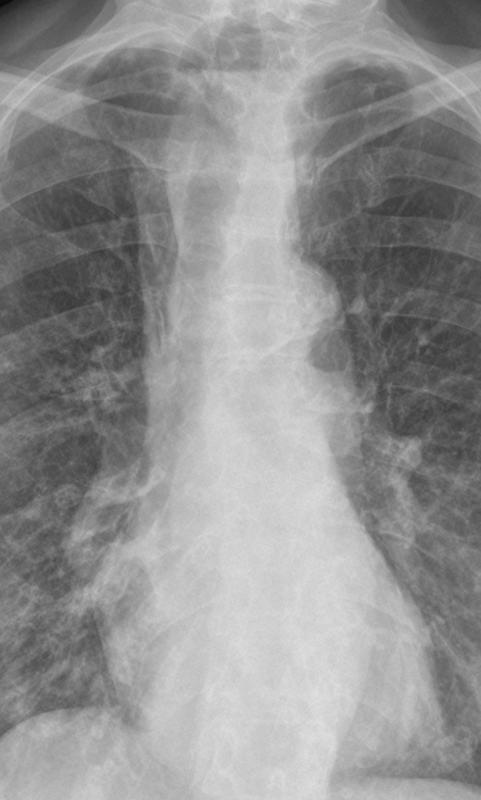

Esoph obstr'n - air-fluid level